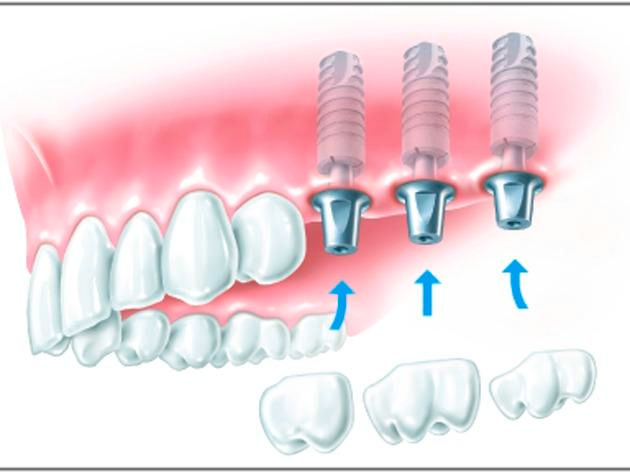

Große Zahnlücke

Wenn das Lächeln plötzlich in die Jahre kommt, mehrere Zähne fehlen oder älterer Zahnersatz immer wieder Probleme macht, können Sie die Zahnreihen mit Hilfe von Implantaten wieder unversehrt aussehen lassen.

Einzelzahnimplantate sind eine elegante Lösung, wenn in einer Reihe mehrere Zähne fehlen: Jeder wird einzeln ersetzt und die ursprüngliche Situation exakt wiederhergestellt. Fehlen drei oder mehr Zähne nebeneinander, können Sie sich auch für eine implantatgetragene Brücke entscheiden. Hierbei werden die neuen Zahnkronen miteinander verbunden und stabil auf zwei oder mehr Implantate gesetzt.

Ein Provisorium schließt die Lücken während der Heilungsphase.

Ist diese abgeschlossen, werden auf den Implantaten dauerhaft die endgültigen Zahnkronen oder die Brücke befestigt.